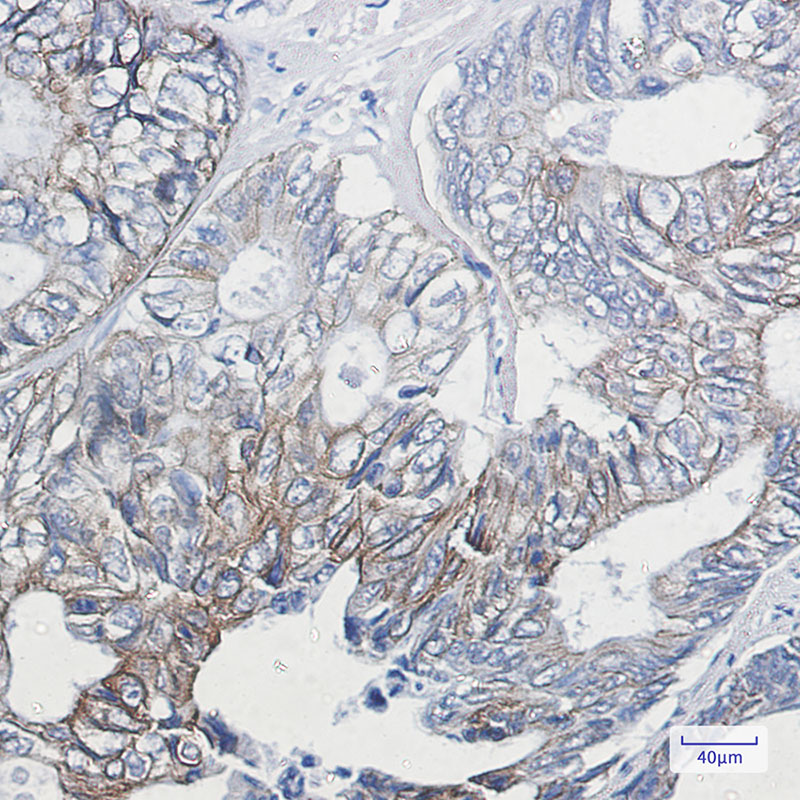

- Immunohistochemistry analysis of paraffin-embedded Human colon cancer using Cytokeratin 8 (Phospho-Ser23) antibody.High-pressure and temperature Sodium Citrate pH 6.0 was used for antigen retrieval.